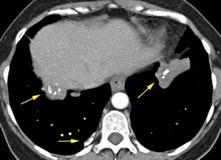

Atropellado. Neumotórax bilateral.

TC: contusión pulmonar severa. Enfisema subcutáneo. Signo del surco profundo

Visible en radiografías en decúbito supino de los pacientes con neumotórax por la acumulación de aire en el seno costofrénico.

“Deep sulcus sign”. Seno costofrénico aumentado en anchura y profundidad

Polireddy K et al. Blunt thoracic trauma: role of chest radiography and comparison with CT findings and literature review . Emerg Radiol 2022.

Kumaresh A et al. Back to Basics – ‘Must Know’ Classical Signs in Thoracic Radiology. Thoracic Radiology. J Clin Imaging Sci 2015.